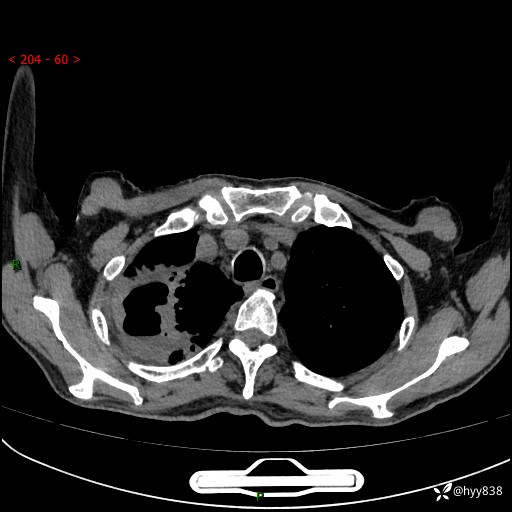

一个月后第二次CT检查(常规抗感染,患者不配合:增强、住院---)

现病史:患者自诉1周前无明显诱因出现咳嗽,伴咳痰,咳白色泡沫样痰,程度不剧烈,痰不易咳出,无发热、畏寒、头晕、头痛、咽痛、胸闷、胸痛、咯血、呼吸困难、四肢酸痛、腹泻、腹痛等不适,起初未予重视,未行相关诊治,1天前患者出现咳嗽,咳痰,痰中带血丝,程度不剧烈,伴食欲减退,恶心,无胸闷气促、无端坐呼吸及夜间阵发性呼吸困难,无明显呕吐,无腹痛腹泻,无血尿黑便及下肢水肿等不适,至我院急诊就诊,行胸部CT提示:右肺上叶感染并空洞形成,遂以“肺部感染”收入我科。 起病以来,患者精神、睡眠可,饮食长期欠佳,小便正常,大便便秘史约1年余,长期予灌肠排便,体力稍下降,体重无明显变化。